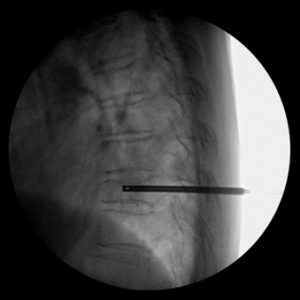

BLUEPECKER PLUS